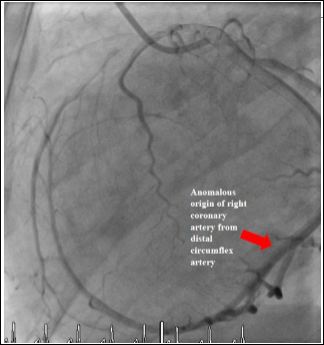

Our first case was a 57-year-old male with a history of moderately severe aortic stenosis presenting with syncope and reduced effort tolerance. Preaortic valve replacement surgery, he had a diagnostic coronary angiogram which revealed an anomalous origin of his right coronary artery from the distal left circumflex artery and a significant left anterior descending artery lesion (Figure 1). The patient underwent successful bioprosthetic aortic valve replacement surgery with coronary artery bypass grafting of Left Anterior Descending artery (LAD).

Figure 1: Anomalous Origin of the Right Coronary Artery from the Distal Circumflex Artery.